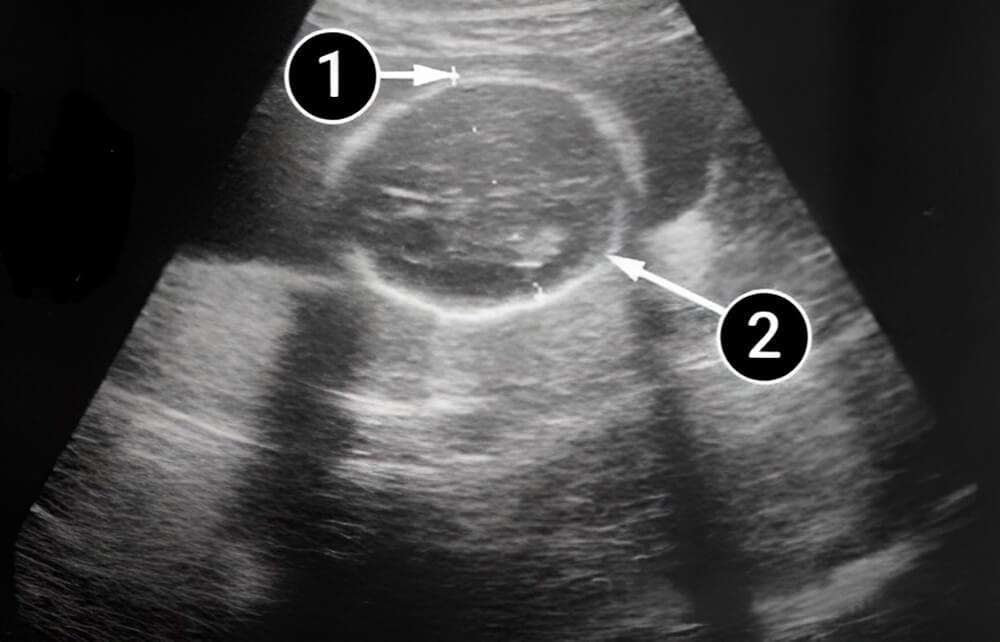

Lo que podemos ver en un ultrasonido

El bebé está acostado de espaldas a la pantalla, lo que permite ver el hombro, la axila, el antebrazo, el codo y la muñeca izquierdos. Ya es más fácil ver el cuello, alrededor del cual poco a poco se va depositando grasa subcutánea.